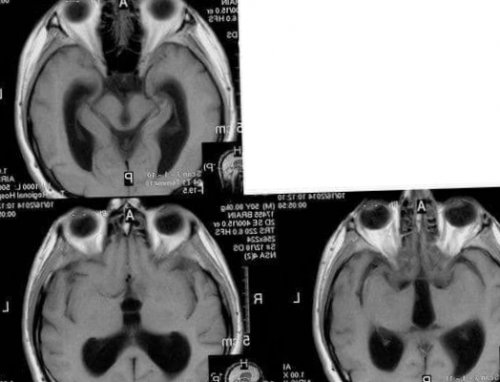

Чтобы опровергнуть или подтвердить сомнительный диагноз, можно пройти обследования на аппарате МРТ, которое покажет все возможные новообразования, их размеры и содержимое, что позволит судить о нарастании давления внутри черепа.

и признакиС целью оттока • петлевые диуретики;облегчения общего состояния Лечебные мероприятия зависят • длительности развития заболевания;Нейрохирурги для лечения гидроцефалии у взрослых применяют малотравматичную нейроэндоскопическую методику – эндоскопическую вентрикулоцистерностомию дна третьего желудочка. В желудочки мозга вводят хирургический инструмент с камерой на конце. С камеры изображение передаётся на монитор, что позволяет точно контролировать все манипуляции. На дне третьего желудочка создают дополнительное отверстие, соединяющееся с цистернами основания мозга. Так восстанавливается физиологический отток ликвора между желудочками и цистернами.Как лечить гидроцефалию головного мозга у взрослых? Начальные стадии гидроцефалии неврологи Юсуповской больницы лечат медикаментозно.• ультразвуковое исследование сосудов головного мозга для определения состояния артериального и венозного кровотока.Врачи Юсуповской больницы проводят диагностику гидроцефалии с помощью компьютерной и магнитно-резонансной томографии. Эти методы позволяют определить размеры и форму желудочков, цистерн мозга субарахноидального пространства. Если врачи клиники неврологии выявляют ранние признаки гидроцефалии на МРТ, они назначают медикаментозное лечение, позволяющее остановить прогрессирование болезни. Рентгенография цистерн основания мозга позволяет уточнить тип гидроцефалии и оценить направление тока ликвора.• быстрая утомляемость;Сообщающаяся гидроцефалия головного мозга у взрослых чаще имеет хроническое течение. Заболевание развивается постепенно, через несколько месяцев после воздействия провоцирующего фактора. Вначале нарушается цикличность сна, появляется сонливость или бессонница. У пациентов ухудшается память, появляется быстрая утомляемость, вялость. По мере прогрессирования заболевания когнитивные нарушения усугубляются вплоть до деменции. Пациенты ведут себя неадекватно и теряют способность к самообслуживанию.• посттравматических состояний и травм головного мозга.• опухолей желудочков и вещества мозга;• сосудистой патологии головного мозга (субарахноидальное и внутрижелудочковое кровоизлияние в результате разрыва неправильного соединения артериовенозных сосудов или аневризм);• гипотензивной (пониженное ликворное давление).